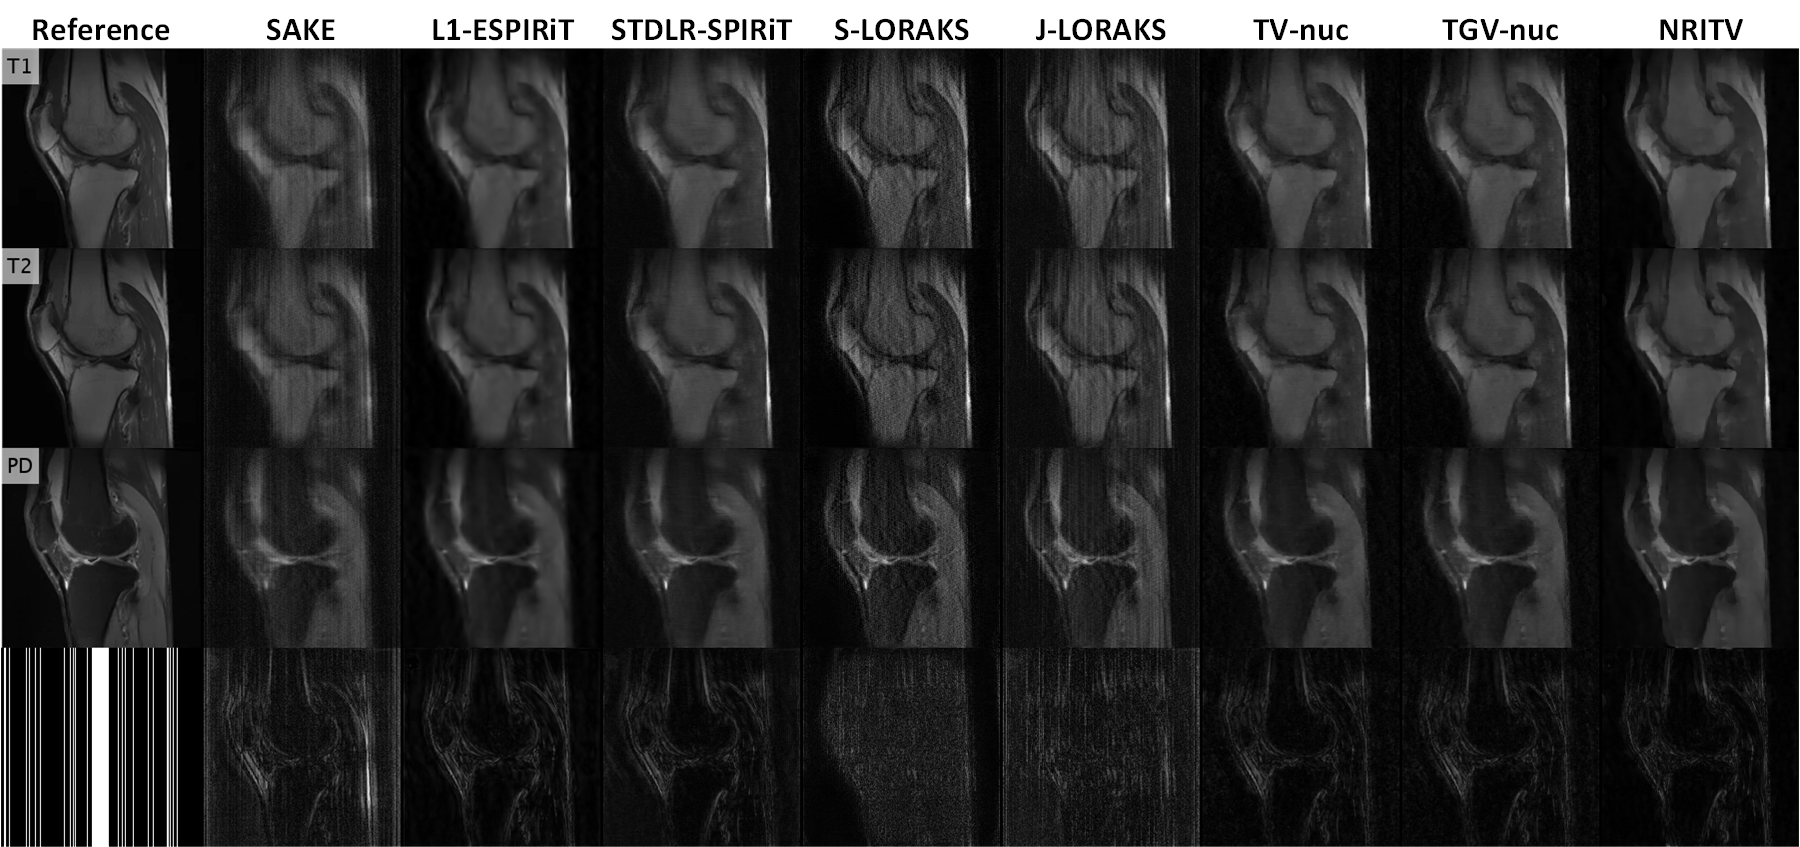

A triple-contrast knee dataset from [12] is used in our next experiment. The data was acquired from GE 3 Tesla scanner (Discovery MR750W, USA) with important parameters TR = 499499499 ms and TE = 9.639.639.63 ms for TSE T1subscript𝑇1T_{1}-weighted contrast; TR = 243524352435 ms and TE = 49.9849.9849.98 ms for T2subscript𝑇2T_{2}-weighted contrast and TR = 225322532253 ms and TE = 31.8131.8131.81 ms for PD-weighted contrast with FOV = 180×180 mm2180180superscript mm2180\times 180\text{ mm}^{2} and slice thickness = 444 mm. As is the way with many MC free-breathing sequences, some degree of involuntary patient movement is anticipated in this dataset. Canny’s edge detection algorithm [29] was used to identify the location of the edges in all three contrasts. In each of the three panels of Fig. 7, the results of edge detection for each of the three possible pairs of images is shown. Disjoint green and blue curves represent mismatched edges, whereas matched edges are colored white. It is clear that T1subscript𝑇1T_{1} and T2subscript𝑇2T_{2} contrasts almost perfectly match but the PD contrast is misaligned with them. The arrows in Fig. 7 mark example regions where the PD-weighted contrast is misaligned with the other two contrasts. This dataset is used to see if the proposed method can sustain some degree of misalignment. To further complicate the situation, white Gaussian noise with σ=0.02𝜎0.02\sigma=0.02 was added and k-space was undersampled at R=5𝑅5R=5. The results are magnified in Fig. 8. SAKE and LORAKS-based methods are again dominated by noise while other compared methods lose contrast (yellow boxes encompassing the patellar tendon in the PD results) and fine details (blue arrows marking the border between tibia and infrapattelar fat in T1subscript𝑇1T_{1} and T2subscript𝑇2T_{2} contrasts). NRITV effectively removes noise without causing any loss of such details. Full-size FOVs, error maps and the sampling pattern related to this experiment are shown in Supplementary Fig. 13. NRITV used λ=5×103𝜆5superscript103\lambda=5\times 10^{-3} while the parameters of the other methods are presented in Table 6. ESPIRiT estimated the maps used in NRITV with 14%percent1414\% RLNE.

Refer to caption

Figure 8: Magnified views of the results for the knee data at R=5𝑅5R=5 and σ=0.02𝜎0.02\sigma=0.02. Some errors in the competing methods and their corrections with the proposed one are marked by arrows and boxes. Appendix Fig. 13 shows full size FOVs, error maps and the sampling pattern for this experiment.